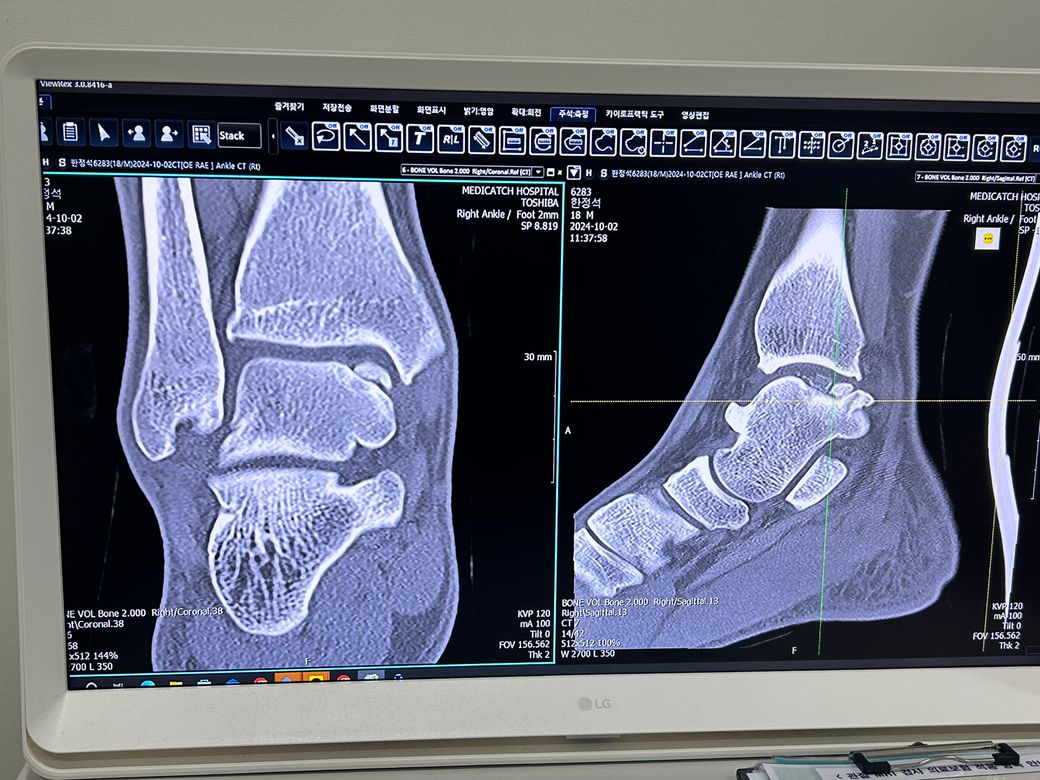

거골의 골연골병변 발목 보호대 무엇을 사용해야 할까요?

경찰이 꿈인 10대 학생입니다. 저번주에 오른쪽

발목의 불편함으로 정형외과에 내원했는데 거골의 골연골병변 진단을 받게되었습니다. 많이 심각하다

하셨지만 고통같은 증상이 적고 수술적 치료는 인공 관절이나 유압 수술같은 큰 수술이 필요하다고

하셔서 고민 끝에 비수술적 치료를 하기로 했습니다. 진로가 경찰인지라 실기 준비를 위해 운동을 오래

• 1번 째 사진

• 2번 째 사진

• 3번 째 사진